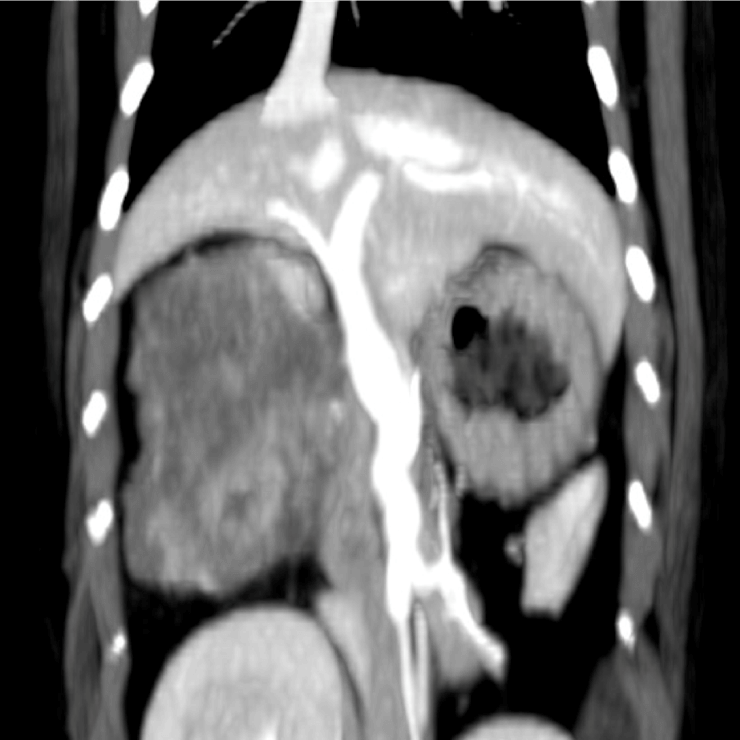

CT(第2病日)

肝動脈尾状葉枝が栄養血管門脈血の流入は確認されず

尾状葉由来5cm大

動脈相

門脈相

CT MIP

【診断・治療方針】

腹腔内腫瘤の破裂による非外傷性出血

― 腹腔内腫瘤は肝尾状葉由来 (Φ5cm)

腫瘤は動脈相で早期膿染

― 肝動脈尾状葉枝が栄養血管